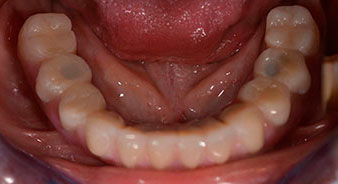

Die 64-jährige Patientin wurde mit einer Unterkiefer-Restbezahnung 38, 33 und 43 und einer klammerbefestigten Interimsprothese im Unterkiefer vorstellig (Abb. 1 und 2).

Abb. 1

Unterkiefer-Restbezahnung